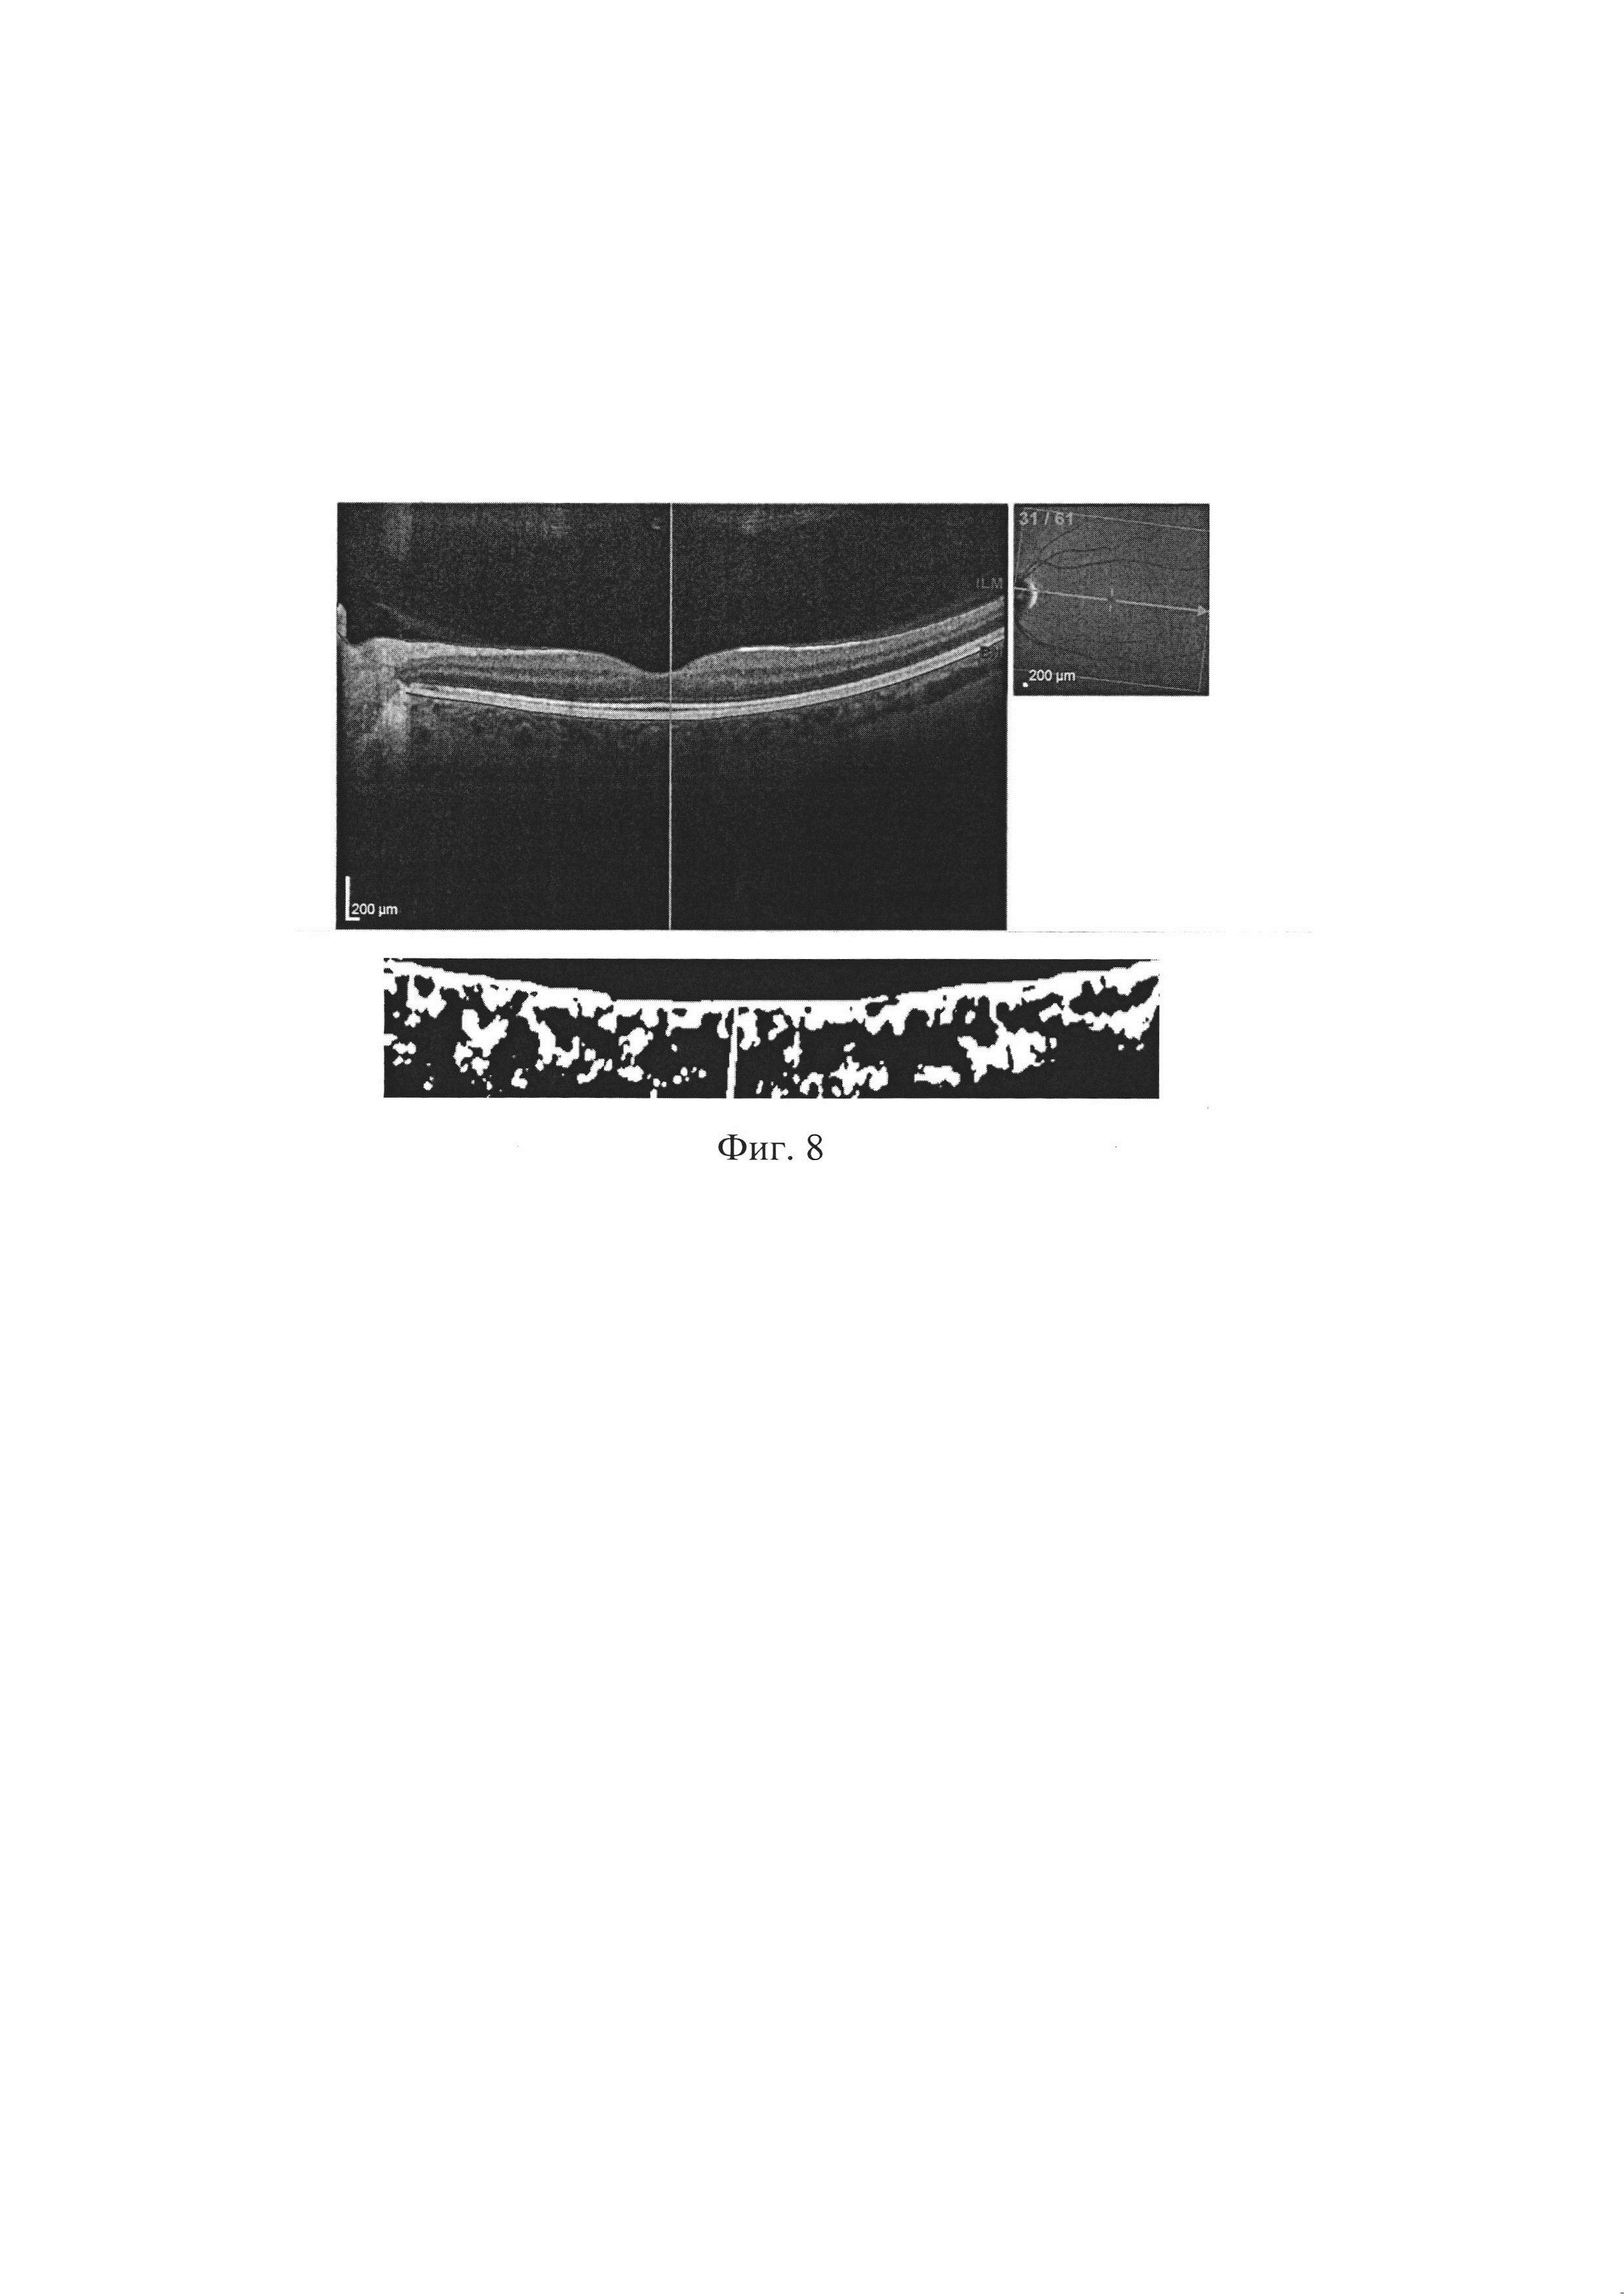

Изобретение относится к медицине, а именно к офтальмологии и неврологии, и предназначено для диагностики рассеянного склероза. Рассеянный склероз (PC) является одной из социально значимых проблем во всем мире. Это тяжелое, хроническое, демиелинизирующее заболевание центральной нервной системы, которое является причиной инвалидизации трудоспособных и социально активных молодых людей. Данное заболевание оказывает огромное влияние на полноценность почти всех категорий жизнедеятельности человека, таких как передвижение, самообслуживание, ориентация в пространстве и общение. Внимание офтальмологов к проблеме диагностики рассеянного склероза обусловлено высокой частотой выявления этого заболевания (от 45% до 80% случаев, по данным различных авторов). Особый интерес представляет тот факт, что оптическая нейропатия, как исход ретробульбарного неврита нередко является клинически изолированным синдромом рассеянного склероза - то есть самой ранней стадией заболевания, при которой уже имеются нейродегенеративные изменения. При длительности рассеянного склероза более 5 лет поражение зрительного анализатора выявляется у 70% больных. Аксоны ганглиозных клеток сетчатки имеют значительную протяженность и оканчиваются синаптическими контактами с ганглиозными клетками наружного коленчатого тела. Длина аксона ганглиозной клетки сетчатки около 75 мм. Аксоны последовательно проходят в трех анатомических структурах: зрительном нерве, хиазме и зрительном тракте. При воспалительном процессе в пучках аксонов или нахождении бляшки рассеянного склероза в зоне прохождения этих аксонов вокруг аксона возникает воспалительный отек и нарушается целостность его миелиновой оболочки. Это приводит к нарушению прохождениянервного импульса (потенциала) по аксону, в результате чего нарушаются зрительные функции. Для рассеянного склероза характерно ремиттирующее течение болезни - сочетание периодов обострения воспалительного процесса со стадиями ослабления воспаления (ремиссией). Быстрое снижение зрения при рассеянном склерозе в период обострения можно объяснить тем, что нарушение зрительных функций связано с преходящим отеком, нарушением миелинового покрытия аксона, а также угнетением функции окружающих аксон олигодендроцитов и астроцитов. Последующее улучшение зрительных функций связано со сравнительно быстрым рассасыванием отека и улучшением функциональных особенностей олигодендроцитов по выработке миелиновых композиций для восполнения образовавшихся дефектов миелинового покрытия аксона. Такое течение заболевания является характерным дифференциально-диагностическим признаком самой распространенной ремитирующей формы рассеянного склероза. Молекулярный субстрат для ремиссий появляется за счет восстановления демиелинизированной оболочки аксона между перехватами Ранвье, которая приобретает большую плотность натриевых каналов. В связи с этим аксон продолжает проводить потенциал, несмотря на малое количество миелина в зоне поражения. Применяя конфокальную микроскопию и реконструируя трехмерное компьютерное изображение, В. D. Тгарр и соавт. показали наличие повреждающих субстанций, воздействующих на аксоны и их миелиновую оболочку головного мозга больных рассеянным склерозом. При использовании антител к нефосфорилированным нервным волокнам (маркеры для участков нервной ткани с недостатком миелина) в стадии активного процесса при рассеянном склерозе было обнаружено обилие воспалительных клеток. Для сохранения аксона и модуляции нейротрансмиттеров имеют значение ионные каналы и ионные обменники. Нарушение этого процесса лежит в основе повреждений аксона. Целостность и функция аксона после его повреждения могут быть сохранены посредством применения нейропротекторов, которые блокируют или модулируют ионные потоки. В зоне поражения аксонов также определяются воспалительный отек, дегенерация и деструкция клеток нейроглии. В воспалительном инфильтрате определяются различные клеточные элементы: лимфоциты, нейтрофилы, макрофаги. В последующем эти клетки входят в состав бляшек рассеянного склероза. При непрогрессирующей форме рассеянного склероза характерно вялое течение воспалительного процесса в очаге поражения. В связи с этим, при неблагоприятном течении рассеянного склероза, выражающемся в длительном снижении зрительных функций, можно выделить 4 последовательные стадий разрушения аксонов, а именно: стадия дистрофии, стадия деструкции, стадия дегенерации на участке демиелинизации аксона. Последняя стадия - атрофия аксона, полностью прерывающая проведение нервного импульса от ганглиозной клетки сетчатки. По всей длине аксона ганглиозной клетки сетчатки, на любом участке от решетчатой пластинки склеры до наружного коленчатого тела, нарушение трофики и целостности миелиновой оболочки является началом патологического процесса в аксоне. В последующем этот процесс с миелиновой оболочки переходит на нервное волокно, что и приводит к нарушению зрительных функций. В наружном коленчатом теле аксоны ганглиозных клеток сетчатки через синаптические связи передают нервный импульс (потенциал) ганглиозным клеткам наружного коленчатого тела. Аксоны ганглиозных клеток наружного коленчатого тела также имеют значительную длину, доходя до корковых структур затылочных отделов головного мозга. Ониобразуют зрительную лучистость Грациоле и оканчиваются синаптическими связями в корковых структурах зрительных областей головного мозга. При поражении рассеянным склерозом отдельных зон этого участка зрительного пути также возникают нарушение проведения нервного импульса и нарушение зрительных функций. При нахождении очага поражения в зрительном нерве снижаются зрительные функции только больного глаза. При поражении зрительного пути в хиазме, зрительном тракте, коленчатом теле и зрительной лучистости Грациоле страдают зрительные функции обоих глаз. Так, немало работ проведено и проводится именно в этом направлении. Пациентам проводят комплексное нейроофтальмологическое обследование, включающее сбор анамнеза и традиционные функциональные и объективные методы диагностики: визометрию, рефрактометрию, кинетическаю периметрию на белый объект и цвета (красный и зеленый), биомикроскопию, офтальмоскопию (Захаров А.В. и др., Оценка рисков трансформации монофокального клинически изолированного синдрома в клинически достоверный рассеянный склероз, Журнал неврологии и психиатрии им. Корсакова, Т. 113, №2, Выпуск 2, 2013 г., с. 28-32; Малов В.М. и др., Новые перспективы ранней диагностики оптического неврита и рассеянного склероза, Неврологический вестник, журнал имени В.М. Бехтерева, Том XLII, №1, 2010 г., с. 72-74), однако результаты данных исследований не могут однозначно свидетельствовать за точность диагноза. Перспективным является направление исследования области зрительного нерва с помощью оптической когерентной томографии, поскольку объективизация и достаточно четкая визуализация получаемых на сканах структур может более достоверно свидетельствовать о развитии заболевания. Так, на уровни техники известен способ диагностики рассеянного склероза (Синеок Е.В. и др., Ранняя диагностика нейродегенеративных изменений при рассеянном склерозе на основе программы диагностики сетчатки, Журнал международной медицины, 2015 г., №2(13), с. 127-130), принятый нами за прототип. Способ заключается в проведении комплексного нейроофтальмологического обследования, включающего оптическую когерентную томографию перипапиллярной области диска зрительного нерва и макулярной области сетчатки на обоих глазах. Кроме того, всем пациентам проводилась оптическая когерентная томография диска зрительного нерва и перипапиллярных нервных волокон сетчатки. Однако, данный способ обладает следующими недостатками. Оценка только параметров сетчатки может привести как к ложноположительным, так и к ложноотрицательным результатам, поскольку данные параметры в целом не позволят провести высокоточную диагностику именно рассеянного склероза. Таким образом, существует потребность в способе диагностики рассеянного склероза, лишенном вышеуказанных недостатков. Техническим результатом настоящего изобретения является повышение точности и достоверности диагностики рассеянного склероза за счет оценки высокочувствительного и специфичного маркера, такого как параметры хориоидеи, обработанные с помощью математической модели. Этот технический результат достигается тем, что в способе диагностики рассеянного склероза, включающем оптическую когерентную томографию перипапиллярной области диска зрительного нерва и макулярной области сетчатки обоих глаз в рамках комплексного нейроофтальмологического обследования, предлагается выбирать компьютерное изображение хориоидеи, проходящее через фовеолу, в центральной части изображения хориоидеи выделяют участок шириной 1500 мкм, центрированном относительно положения фовеолы; осуществляют предварительную обработку изображения с помощью компьютерной программы количественной обработки состояния сосудов хориоидеи на компьютерных изображениях оптической когерентной томографии глазного дна; на ранее указанном участке определяют толщину хориоидеи в макулярной области (choroidal thickness - СТ), а также удельную долю просветов кровеносных сосудов от общей площади, занимаемой хориоидеей на изображении (proportion of blood vessel lumens in the choroid - PBVLC), после чего вносят полученные значения в формулу где Р - хориоидальный показатель рассеянного склероза, и при значении Р>0,575 хотя бы на одном глазу диагностируют рассеянный склероз. На фиг. 1-2 показаны моменты центровки скана и его обработки в компьютерной программе. На фиг. 3-8 показаны иллюстрации к клиническим примерам. Способ осуществляют следующим образом. В рамках проведения комплексного нейроофтальмологического обследования проводят оптическую когерентную томографию заднего сегмента глаза перипапиллярной области диска зрительного нерва и макулярной области сетчатки (мы проводили исследование с помощью оптического когерентного томографа Spectralis OCT BluePeak (Heidelberg Engineering, Германия)). После этого выбирают компьютерное изображение хориоидеи, проходящее через фовеолу, осуществляют его предварительную обработку в «Программе количественной обработки состояния сосудов хориоидеи на компьютерных изображениях оптической когерентной томографии глазного дна» (свидетельство о гос. регистрации программ для ЭВМ №2017611818 от 09 февраля 2017 г.) Перед обработкой проводят центровку изображения хориоидеи относительно положения фовеолы, для исследования выделяют участок шириной 1500 мкм (Фиг. 1). После обработки (Фиг. 2) определяют с помощью программы толщину хориоидеи в макулярной области СТ (choroidal thickness), а также удельную долю просветов кровеносных сосудов от общей площади, занимаемой хориоидеей на скане PBVLC (proportion of blood vessel lumens in the choroid). Уменьшение толщины хориоидеи и увеличение удельной доли просвета кровеносных сосудов от общей площади хориоидеи вследствие атрофии паренхимы свидетельствует об изменении кровообращения хориоидального тракта при демиелинизирующих заболеваниях. Полученные значения вносят в формулу где Р - хориоидальный показатель рассеянного склероза. Такой подход дал возможность увеличить прогностическую значимость показателей толщины хориоидеи и удельной доли просветов кровеносных сосудов, так как при использовании обоих показателей в вышеуказанной математической модели, значения чувствительности и специфичности для показателя Р составили 94,6% и 90,3% соответственно, в сравнении со считавшимися ранее максимально чувствительными и специфичными показателями морфометрии сетчатки (см. Таблицу 1). Таким образом, в данном способе диагностики рассеянного склероза важен анализ показателей состояния хориоидеи. Пример 1. Пациентка В., 34 лет, поступила в неврологическое отделение МОНИКИ с жалобами на снижение чувствительности в области правого предплечья и контрастности зрения правого глаза. Пациентке было назначено дополнительное обследование, в которое входило МРТ головного мозга с контрастированием и осмотр офтальмолога. На офтальмологическом осмотре острота зрения составила 1,0 на обоих глазах. ВГД OU- 16 мм рт ст. Биомикроскопия и офтальмоскопия не выявили изменений со стороны переднего и заднего отделов глаза. По результатам компьютерной периметрии не обнаружено скотом, сужения полей зрения или снижения светочувствительности на правом глазу. При проведении оптической когерентной томографии на правом глазу зафиксировано снижение толщины перипапиллярных нервных волокон в височном квадранте до 55 мкм. А также изменения общего макулярного объема, который составил 7,59 мкм3, уменьшение объема внутренних слоев сетчатки: объем ганглиозного слоя - 0,82 мкм3 и внутреннего плексиформного слоя сетчатки - 0,71 мкм3 (Фиг. 3). Для диагностики по предлагаемому способу рассчитали показатель Р. Для этого с помощью программы (Фиг. 4) были измерены толщина хориоидеи СТ (221,08 мкм) и удельная доля просветов кровеносных сосудов PBVLC (0,585), показатель Р на правом глазу составил 0,768. Для левого глаза (Фиг. 5) данные соответственно составили СТ (220,28 мкм), PBVLC (0,633), показатель Р на левом глазу составил 0,997. Согласно полученным показателям, у пациента диагностирован рассеянный склероз предлагаемым способом. Через неделю, после проведения МРТ с контрастированием, данный диагноз был подтвержден: Мр-картина многоочагового поражения белого вещества головного мозга с наличием супратенториальных очагов и вовлечением в процесс мозолистого тела, без признаков активности (нарушения ГЭБ), по критериям диагностики соответствует рассеянному склерозу. Таким образом, установлен диагноз: рассеянный склероз, ремитирующего течения, назначена соответствующая терапия. Пример 2. Пациентка А, 25 лет, поступила в офтальмологическое отделение МОНИКИ с жалобами на частые головные боли, периодические боли в области правого глаза и сужение полей зрения, а также боли в спине и правом предплечье. Для постановки диагноза было назначено МРТ с контрастом, консультация офтальмолога. На момент осмотра жалоб со стороны органа зрения пациента не предъявляла, острота зрения составила 1,0 на обоих глазах, ВГД на по Маклакову OU- 18 мм. рт.ст. С помощью биомикроскопии и офтальмоскопии не удалось выявить изменений со стороны органа зрения. По данным ОКТ изменений со стороны зрительного нерва (толщины перипапиллярных нервных волокон в височном квадранте - 73 мкм), сетчатки (объем ганглиозного слоя - 1,95 мкм3 и внутреннего плексиформного слоя сетчатки - 0,95 мкм3). (Фиг. 6). Для диагностики по предлагаемому способу рассчитали показатель Р. Для этого с помощью программы (Фиг. 7) были измерены толщина хориоидеи СТ (438,85 мкм) и удельная доля просветов кровеносных сосудов PBVLC (0,626), показатель Р на левом глазу составил 0,012. Для правого глаза (Фиг. 8) данные соответственно составили СТ (452,26 мкм), PBVLC (0,617), показатель Р на левом глазу составил 0,006. Заключение МРТ: MP-признаков патологических изменений головного мозга не выявлено. С диагнозом идиопатическая головная боль (мигрень с аурой) и назначена терапия. С помощью предлагаемого способа было обследовано 68 пациентов с диагнозом рассеянный склероз с ремиттирующим течением, из них 43 женщины (63%) и 25 мужчин (34%), в среднем возраст мужчин составил 34,9 года, женщин - 33,7. Статистически значимые различия по описанным показателям между мужчинами и женщинами в выборке пациентов не обнаружено. Для сравнения была взята контрольная группа из 23 здоровых лиц с отсутствием офтальмологической патологии после комплексного обследования (визометрия, тонометрия, пахиметрия, компьютерная периметрия, офтальмоскопия, оптическая когерентная томография). Всем пациентам была проведена МРТ с контрастированием. В результате данного исследования была доказана высокая чувствительность и специфичность показателей хориоидеи, обработанных с помощью математической модели, для диагностики рассеянного склероза. Таким образом, предлагаемый способ позволяет повысить точность и достоверность диагностики рассеянного склероза за счет высокочувствительного и специфичного параметра, такого как оценка хориоидеи, а именно ее параметров, обработанных с помощью математической модели.